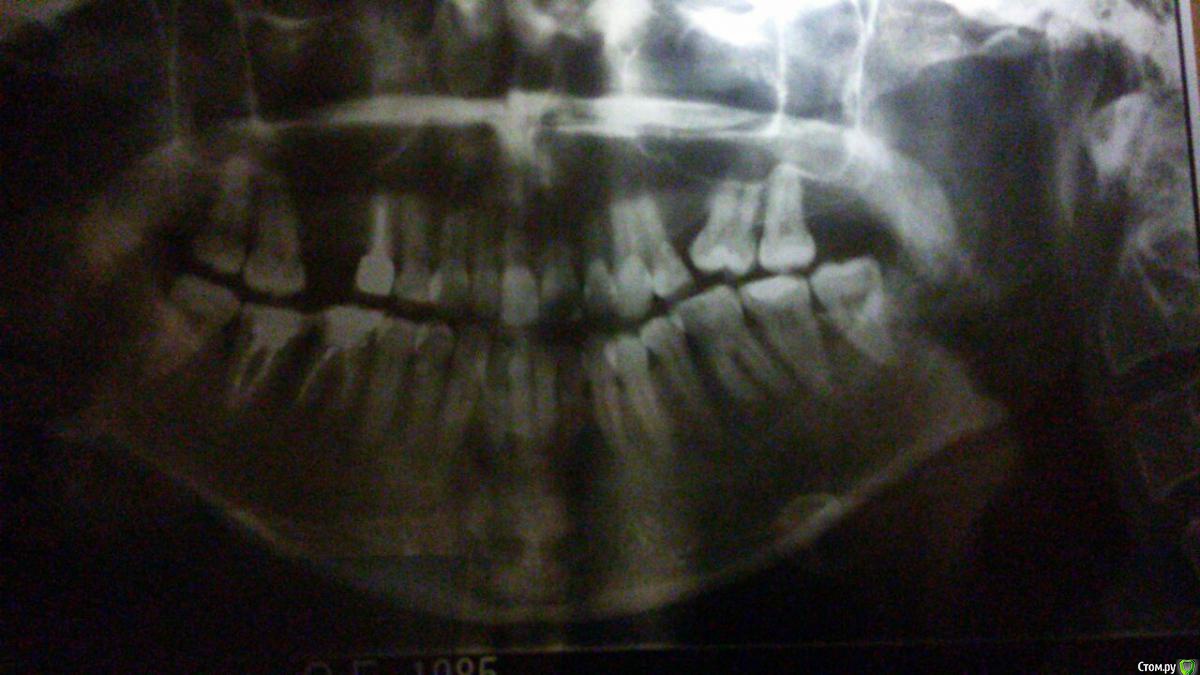

Allegro23 Опубликовано 22 октября, 2016 Поделиться Опубликовано 22 октября, 2016 Доброго дня всем. Прошу совета в такой ситуации: 31 мая 2016 года удалили 6 зуб справа на верхней челюсти, нашли там давно оставленный после удаления нерва инструмент, началось воспаление после перепломбирования. Соседний 5 зуб дважды протезировался, но в итоге неудачно. Неправильно сделанная вкладка дала трещину в корне, плюс обнаружили гранулему. 2 октября 5- зуб удалили. Вопрос такой: когда стоит имплантировать? Врачи говорят разное. кто-то советует ждать 6 месяцев. А кто-то готов провести имплантацию через месяц. Что бы вы посоветовали? С учётом того, что с момента удаления шестёрки прошло уже почти 5 месяцев. Заранее всем благодарна за комментарии. Прилагаю снимок (сделан 16 сентября) и скриншот КТ (сделано 30 сентября, до удаления 5 зуба). Ссылка на комментарий